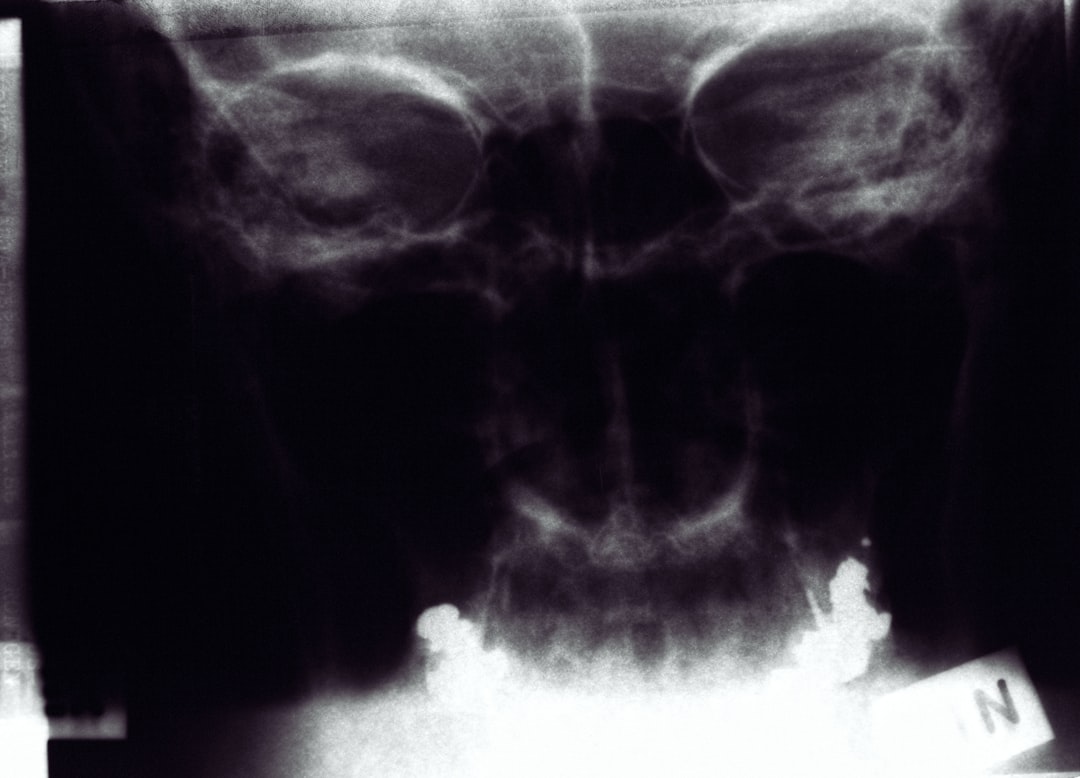

또한, 소변이나 배변 시 불편함도 일어날 수 있습니다. 이는 난소가 크기 때문에 인근 장기와 신경에 영향을 줄 수 있기 때문입니다. 난소종양이 의심되는 증상이 지속된다면, 초음파나 CT 촬영 등의 정밀 검사를 통해 상태를 확인해야 합니다. 이러한 증상들은 건강에 큰 영향을 미칠 수 있으므로 소홀히 여겨서는 안 됩니다.

이 때, 난소암 진단비용은 검사 종류와 의료기관에 따라 차이를 만듭니다. 초음파, 혈액 검사, MRI 등의 비용을 사전에 체크해보는 것이 좋으며, 보험 등을 통해 도움을 받을 수 있습니다. 치료 방법에 따라서도 비용이 차별화되므로 미리 계획하고 준비하는 것이 필요합니다.